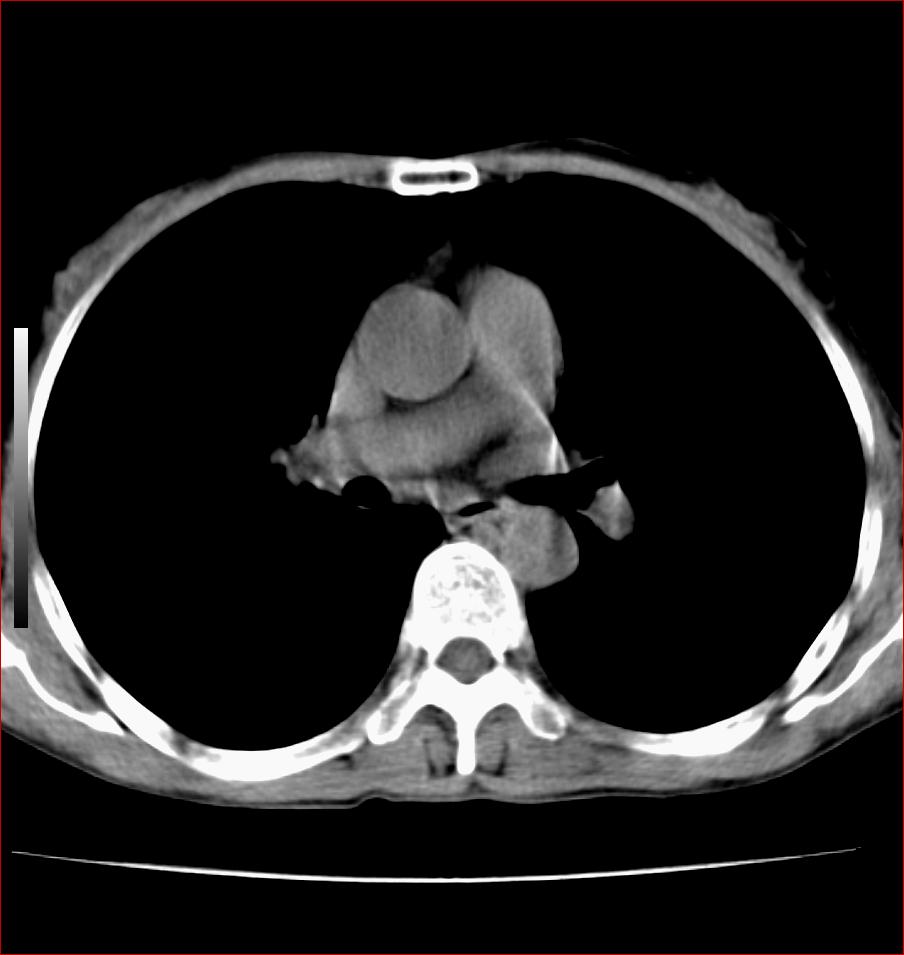

标题: CT17110:F56Y,纵隔囊肿;胸腺?淋巴?请各位老师看看 [打印本页]

标题: CT17110:F56Y,纵隔囊肿;胸腺?淋巴?请各位老师看看

女性患者 56 咽痛伴声嘶10+天入院。

右上纵隔囊性占位性病变;考虑支气管囊肿可能。

病变紧贴气管右壁,两者相互压迫,考虑支气管囊肿!

见相互挤压征,考虑气管囊肿,建议ct增强扫描